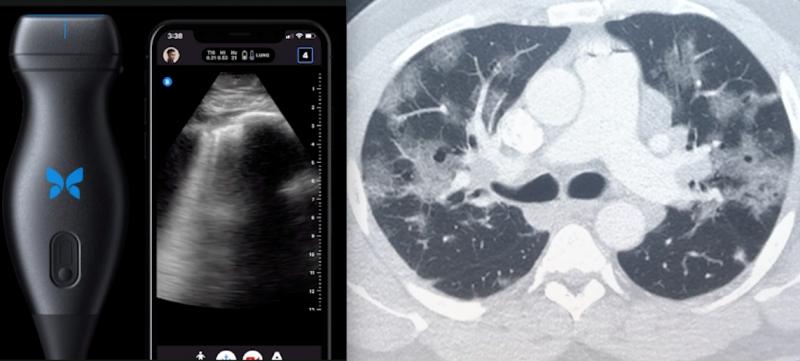

Teleradiology allows radiologists to share radiological patient images from one location to another. This allows them to provide service without being present and also allows them to share studies with other radiologists and physicians.

Teleradiology is grabbing significant eyeballs, given the tremendous potential it exhibits in revolutionizing cancer ...

March 30, 2021 — Nines announced the 510(k) FDA clearance for NinesMeasure, an innovative lung nodule measurement tool ...